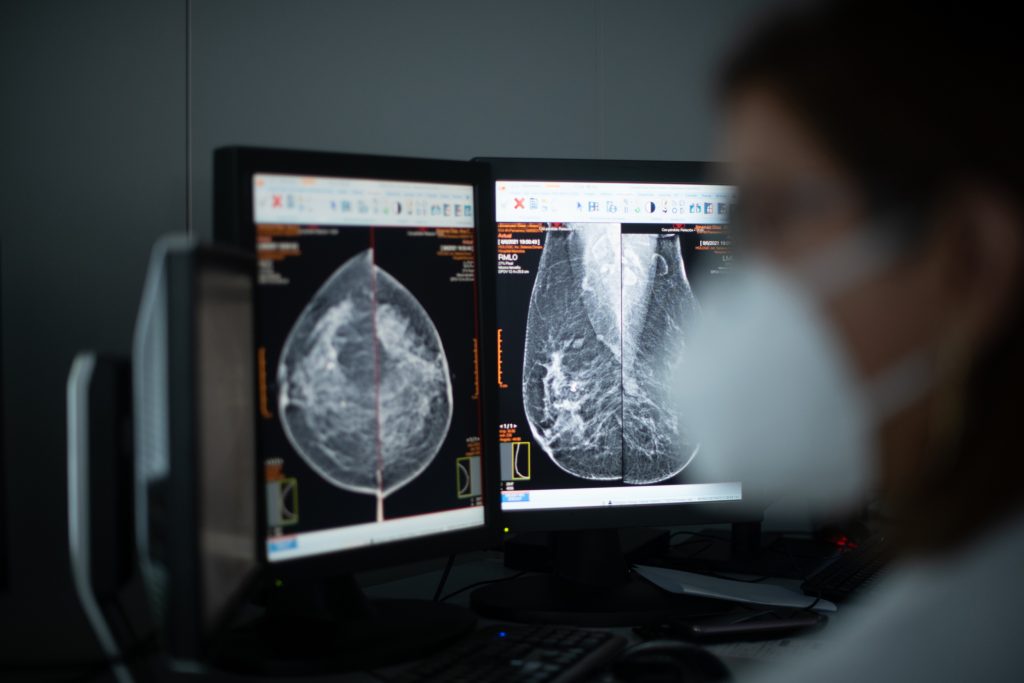

La mamografía en el cribado de cáncer de mama

En la actualidad no existe ninguna duda de que la mamografía es la prueba de cribado más efectiva. Javier de Santiago, presidente de la sección de Ginecología Oncológica y Patología Mamaria de la Sociedad Española de Ginecología y Obstetricia y jefe de servicio del MD Anderson Cancer Center de Madrid, aclara que hay que diferenciar dos tipos de cribado del cáncer de mama:

- El poblacional, a través del cual los responsables sanitarios de las comunidades autónomas convocan a las mujeres para que acudan a un lugar determinado a hacerse una mamografía.

- El oportunista, que consiste en aprovechar la consulta ginecológica para valorar el riesgo de cáncer de mama de una mujer concreta y, en caso de que se estime necesario, pedirle una mamografía.